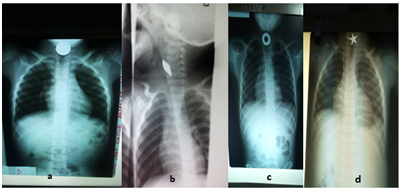

In this study, FB were frequently located in cervical oesophagus (75.68%) as shown in Table 1. The clinical signs observed among children with a FB in their DT were: hypersalivation (84.85%), dysphagia (42.42%), and odynophagia (27.27%). The foreign body was only inorganic (100% of cases). Coin was the main type of FB (74.29%). Table 2 shows the distribution of FB in UDT among children according to their nature. More than half of children (60%) consulted within the first 24 hours, 5.41% between 24 and 48h. 37% of them were admitted beyond 48 hours (Table 3). Frontal and lateral cervico-thoracic x-rays were realized for all the patients and show in 100% of cases, an opacity corresponding to the foreign body at all levels. Figure 2 below presents some cases of FB images.

Figure 2 Cervico-thoracic x-rays showing some foreign bodies a: coin, b: metal sheet, c: metal washer, d: metal bead.